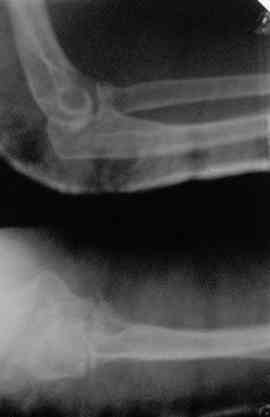

Вывих предплечья

Доброго времени суток, коллеги! Поступила больная2 дня назад (см. снимки).

Вывих вправил, сделал КТ и... появился ряд вопросов: 1.Убирать или оставить отломки? Я думаю убирать2.Каким доступом идти?Что скажете про трасолекрональый?3.Кто какие видел результаты после подобного перелома?4.Что делать с венечным отвостком?5.Нужна ли дополнительная внешняя фиксация?С уважением Д.Б.